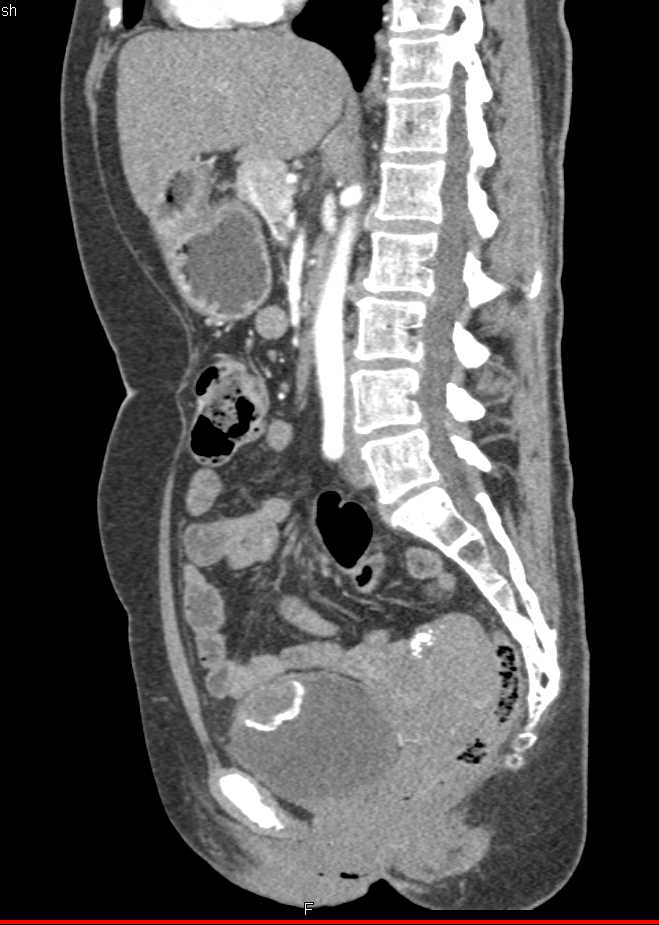

Urachal Carcinoma of the Bladder